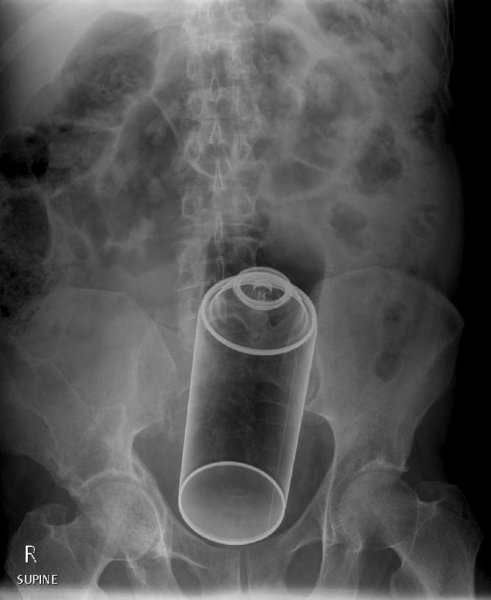

Специалисты по рентгеновской диагностике регулярно сталкиваются с посторонними предметами внутри тела человека. Обычно лишние предметы попадают в пищеварительную систему из-за неосторожности при еде или во время неудачных любовных игр. Почти всё удается вытащить — с хирургическим вмешательством или без него. выбрал самые необычные находки радиологов, которыми они делились на сайте Radiopaedia.org.